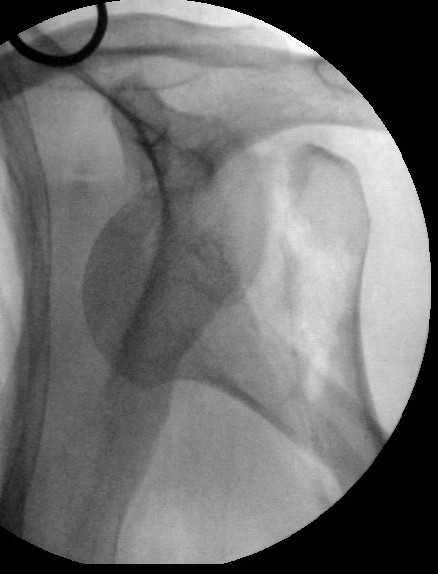

Дорогие коллеги,Мужчина 44 л. упал с крыши дачи 6 августа. Картинки в приложении. Лет 5 назад нде-то оперирован по поводу привычного вывихв этого же плеча.После операции не вывихивал до этой травмы.Как тут лечить? Есть ли шансы на закрытое вправление? Чем лучше фиксировать? Какие меры принять с учетом бывшего и нынешнего вывиха? Заранее спасибо. Dear colleagues, A male 44 y.o. admitted to our unit. Injured at Aug. 6 - fall from 3 m. Images attached. Five years ago was operated somewhere else for recurrent dislocation of thу same shoulder, no data what was done. What would be optimal treatment option? Any chance of closed reduction? What should be done to address the current and past dislocations? THX.

I would recommend an initial attempted closed reduction in the OR with fluoroscopy. It is important that this is done in a controlled fashion to make sure you are not further displacing the head and leaving it behind. If

you can get it reduced then you will have a much better ability to understand the fracture and possible glenoid involvement. I think regardless

of getting the humeral head reduced this fracture should be managed operatively with plate fixation of the tuberosity fragment and a combination of lag screw and plate fixation of the proximal shaft extension. My concern is that treating it conservatively after closed reduction will lead to issues of instability and malunion given the size of the tuberosity fragment and past history.

I would also not be surprised if there was some glenoid issues related to the prior instability. It is difficult to tell on the provided xrays. Either a CT scan or an Axillary view should be done to assess this prior to definitive surgery.

This is an anterior fracture/dislocation with shaft extension-no chance for closed reduction-probably contraindicated, especially since the injury is now 19 days old. We do these supine on a radiolucent table with an arm board extension-you now have an unobstructed radiographic view of the entire upper extremity both AP and lateral with excellent axillary views of the glenohumeral joint to assess your reduction and screw placement. This is the perfect indication for a locking plate via the traditional deltopectoral approach. Use the biceps tendon to stay anatomically oriented during the approach and be sure to check the rotation post plate application. In general, we have not performed any soft tissue stabilization procedures during the fixation, may stay away from external rotation past neutral during rehab and early motion protocol. This one should do fine.